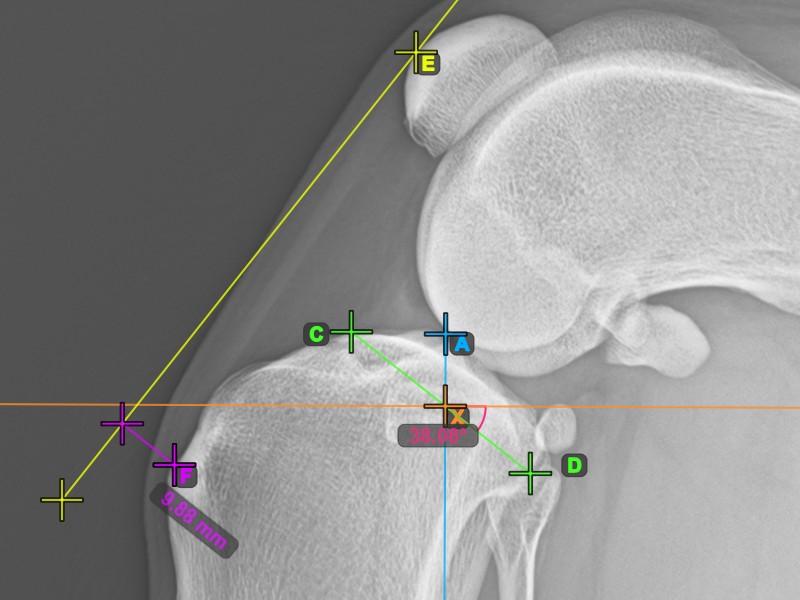

Vervollständigen Sie den TPA-Winkel, indem Sie den hintersten Punkt des Tibiakopfes (Tibiaplateau) markieren. Der TPA-Winkel wird automatisch als der Winkel zwischen der Linie, die die beiden Punkte am Tibiaplateau verbindet, und der senkrechten Linie zur Längsachse der Tibia berechnet.

Das Bild unten zeigt die übliche Platzierung des hintersten Punkts am Tibiaplateau und die automatisch berechnete TPA-Winkel-Messung.